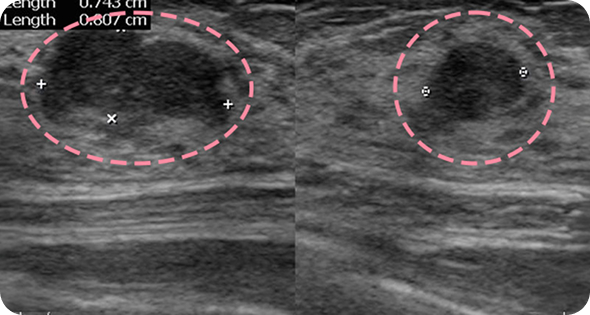

영상 특화 전문의니까

초음파 보면서

맘모톰도 안전하게

양성 종양은 여러 개가 동시에 생겨나기도 합니다. 정상적인 유방 조직 보전에 신경 쓰며 맘모톰 시술을 섬세히 진행했고, 6개월 뒤 추적 관찰을 위한 유방초음파에서 종양이 깨끗이 제거된 것을 확인했습니다. 일부 반흔 조직은 자연스럽게 호전될 것으로 보여 좋은 예후가 기대되었습니다.